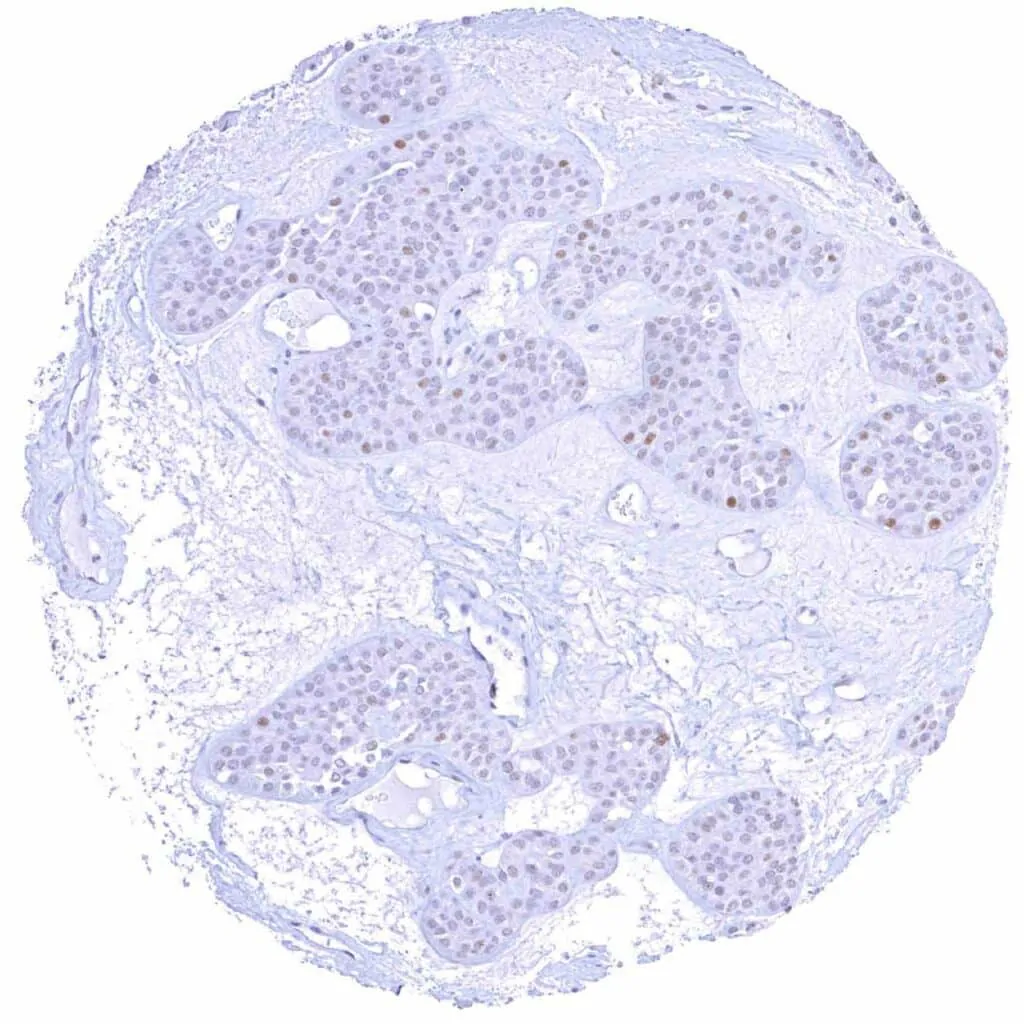

Breast – Invasive breast cancer of no special type (NST) with faint Cyclin E1 immunostaining of few tumor cells